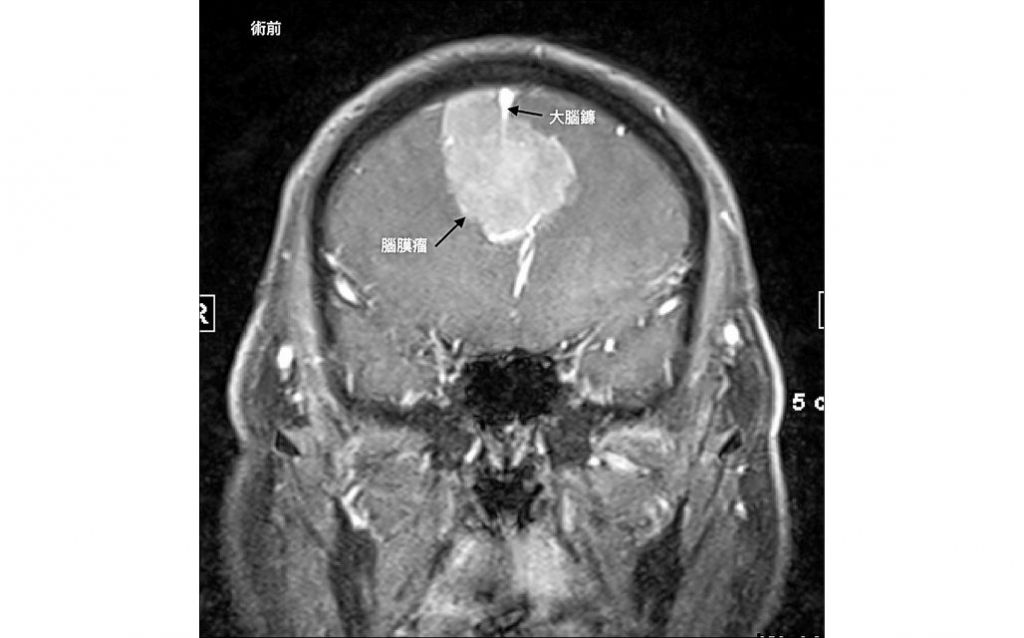

結果發現一個位在中線的大腦鐮腫瘤,進一步做核磁共振檢查之後,判斷是一個直徑6公分而且跨越中線的大腦鐮腦膜瘤合併雙側前額葉的腦水腫 (圖1)。因此,我們進行雙側前額葉的開顱手術把腫瘤從兩邊切除(圖2)。

大腦鐮是一個鐮刀狀的結構,位在大腦中間分隔兩側大腦。而大腦鐮腦膜瘤起始於大腦鐮旁,由於位置較深而生長緩慢,腫瘤較小時一般不引發明顯的臨床症狀,因此發病時,腫瘤往往已長得較大,出現運動障礙時,會從足部開始,逐漸影響整個下肢。由於病人沒有下背痛和神經痛的症狀,很容易和脊椎問題造成的下肢無力區別。

大腦鐮腦膜瘤會長到兩側的並不多見。阿春伯的症狀有一部分因為對兩側前額葉擠壓而造成下肢運動控制不良,使他不良於行;而對兩側前額葉的神經壓迫造成個性改變、人格異常及記憶缺損,但因從事務農工作,很少需要太多計算,他還是可以完成日常的工作,只是偶爾會露出他那神秘的微笑,直到他不能走動了,才被送醫。